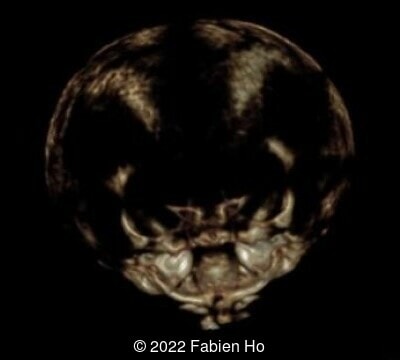

- Low bone density of skull and lower limbs

Characteristics of osteogenesis imperfecta that can be identified prenatally include early onset of severe long bone shortening and bowing due to multiple intrauterine fractures, narrow thorax, normal head circumference but abnormal translucency and compressibility [8,9]. The poor mineralization of the skull leads to deformation of the head by the ultrasound transducer [10]. The diagnosis can be made as early as the first to early second trimester [11]. Several cases have also been documented in the literature that associate osteogenesis imperfecta with an increased nuchal translucency in the first trimester [12].